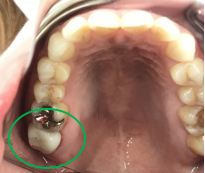

男性 Mさん 50代 (オールセラミック冠)

主訴

右上奥歯が、冷たいものにしみる。

治療内容

歯髄(神経および血管)まで到達する大きな虫歯でしたので、抜髄(歯髄を取り除く)をし、ファイバーコアをいれ、オールセラミック冠を被せました。

所感

現在、保険治療において、限定的ではありますが、大臼歯にも白い被せ物(プラスチック冠)ができるようになりました。しかし、実感としてプラスチック冠は、

- すり減りやすい。割れることがある。

- バイオフィルム(細菌およびそれから産生される副産物の塊)が付着しやすいので、歯周病および2次カリエス(被せ物と自分の歯の境目から再度虫歯になる)になるリスクが高い。

- 変色する。

という点を感じます。白い被せ物が保険の治療でできるという理由で、安易にプラスチック冠を選択し、割れたりすり減ったり、変色したらもう一度被せなおせばいいと考えるのであれば、一度立ち止まって考えてみてください。歯の量は、治療するたびに薄く少なくなり、歯根破折のリスクが高まります。もし大きな虫歯になってしまったら、最高レベルの根管治療をし、最良の被せ物であるオールセラミック冠を被せ、定期的にお口の中のクリーニングをし、同じ歯を2度と治療しないことが、歯を長持ちさせる最良の方法だと考えます。

オールセラミック冠(失活歯):¥104,500(税込)

Before

劣化したプラスチック冠

After